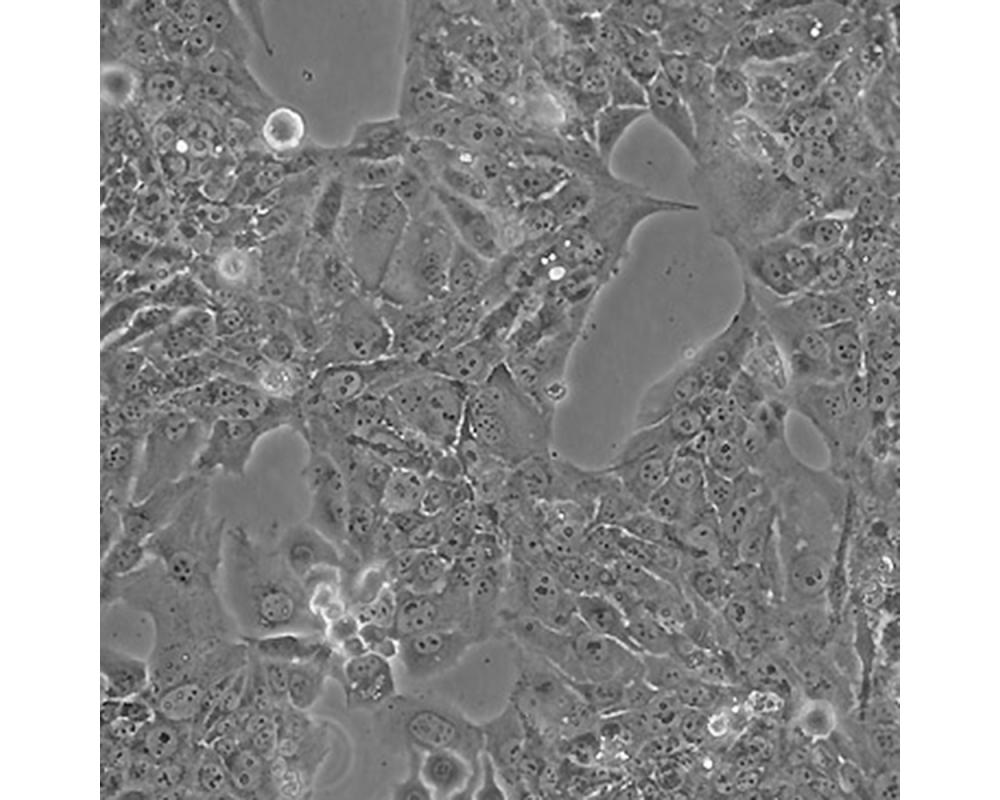

BeWo

中文名稱 人胎盤絨膜癌細胞

組織來源 妊娠性絨癌

形態特征 上皮樣

生長特性 貼壁生長

特征特性 取自人絨癌腦轉移組織,在倉鼠頰囊移植傳代8年。利用移植瘤組織進行體外培養,建立細胞系。利用不同傳代方法建立了不同亞系,JEG-3是其衍生克隆。該細胞可以產生雌激素、孕激素、雌酮、雌二醇、雌三醇、hCG、胎盤催乳素、角蛋白。